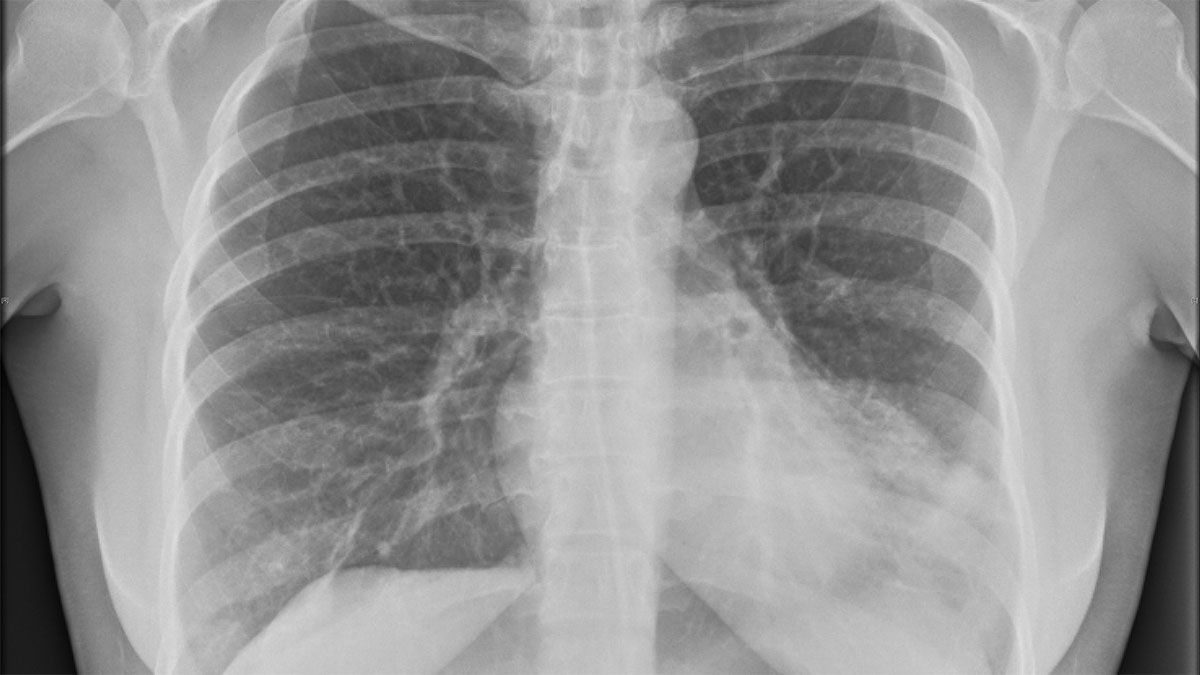

Un informe publicado en la Biblioteca Nacional de Medicina revela que a una mujer de 27 años, que había llegado al hospital con tos, fiebre y una mucosidad espesa persistente desde hacía seis meses y a la que le habían recetado antibióticos y tratamiento antituberculoso que no tuvieron ningún efecto, finalmente le encontraron la causa del problema tras una radiografía de tórax.

Según el informe médico, el esputo de mujer, una maestra de la escuela, fue examinado para detectar tuberculosis pero resultó negativo. Sin embargo, cuando le escanearon el pecho a través de una radiografía, encontraron una lesión en el lóbulo superior derecho de sus pulmones.

Tras una mayor investigación, parecía ser "una estructura en forma de bolsa invertida asentada en el bronquio". Los especialistas extrajeron la misteriosa "bolsa". Y pese a que la mayor parte fue destruida por el proceso, se pudo identificar que era un preservativo, según cuenta el sitio Iflscience.